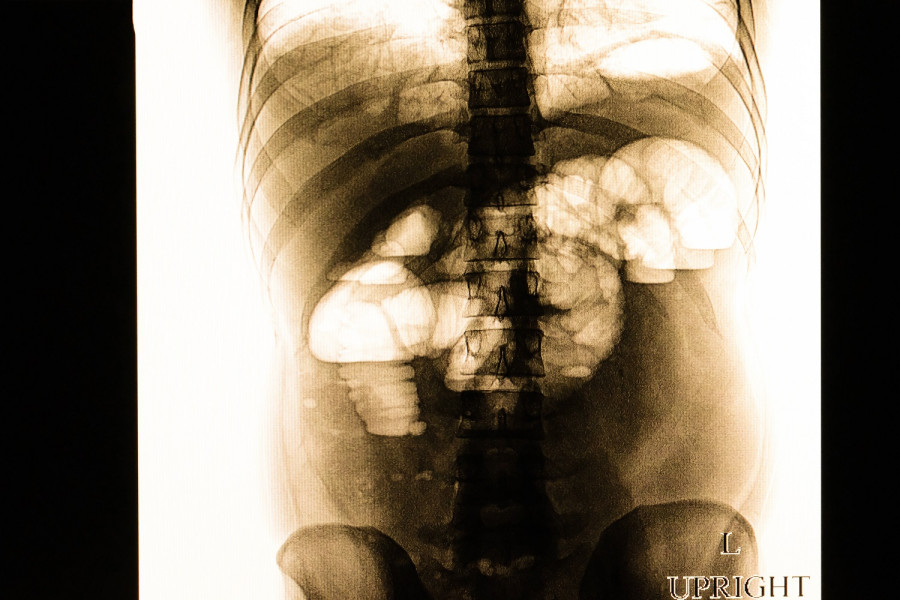

Διάγνωση ειλεού

Ο γιατρός σας θα χρησιμοποιήσει ένα στηθοσκόπιο για να ακούσει τους ήχους που κάνει η κοιλιά σας. Η απουσία ήχου μπορεί να αποτελεί ένδειξη ειλεού. Εάν υπάρχει ανησυχία ότι μπορεί να έχετε ειλεό, ενδέχεται να σας παραπέμψουν για κάποιες από τις παρακάτω εξετάσεις:

- Απεικονιστικές εξετάσεις, όπως ακτινογραφίες κοιλίας και αξονικές τομογραφίες κοιλίας, για τη λήψη εικόνων των εντέρων